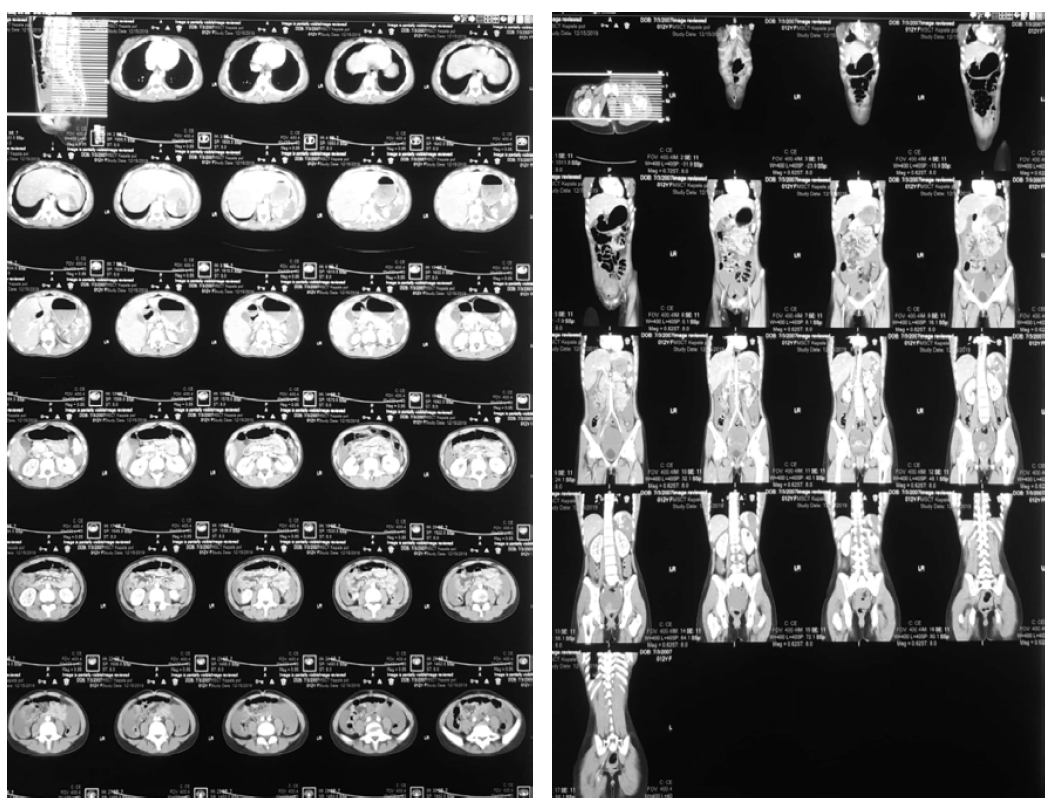

Then, the patient was sent to radiology for abdominal CT examination. The results showed grade IV Spleen Injury (AAST rating scale) and free fluid in the abdominal cavity (Hematoperitoneum) (Figure 2).

Figure 2: Spleen Rupture Grade 4 (AAST Grading Scale), Free Fluid in the Abdominal Cavity (hematoperitoneum)

Then, the patient was sent to radiology for abdominal CT examination, with results showing spleen injury grade V (AAST rating scale) and free fluid in the abdominal cavity (Hematoperitoneum) (Figure 4).

Figure 4. Spleen Rupture Grade 5 (AAST Grading Scale), Free Fluid in the Abdominal Cavity (Hematoperitoneum)

Later, the patient was sent to radiology for abdominal CT examination, and the results showed liver rupture grade IV and splenic rupture grade II (AAST rating scale), with free fluid in the abdominal cavity (Hematoperitoneum) (Figure 6).

Figure 6: Liver Rupture Grade IV and Splenic Rupture Grade II (AAST Rating Scale), Free Fluid in the Abdominal Cavity